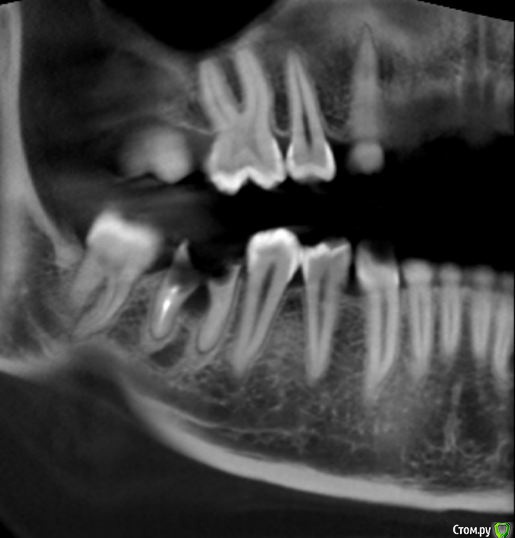

Aleksey_Mironov Опубликовано 22 ноября, 2017 Автор Поделиться Опубликовано 22 ноября, 2017 pan Ссылка на комментарий

Kovalov Igor Опубликовано 26 ноября, 2017 Поделиться Опубликовано 26 ноября, 2017 я бы через 2 месяца имплантировался... по бифуркации не нравится картина Ссылка на комментарий